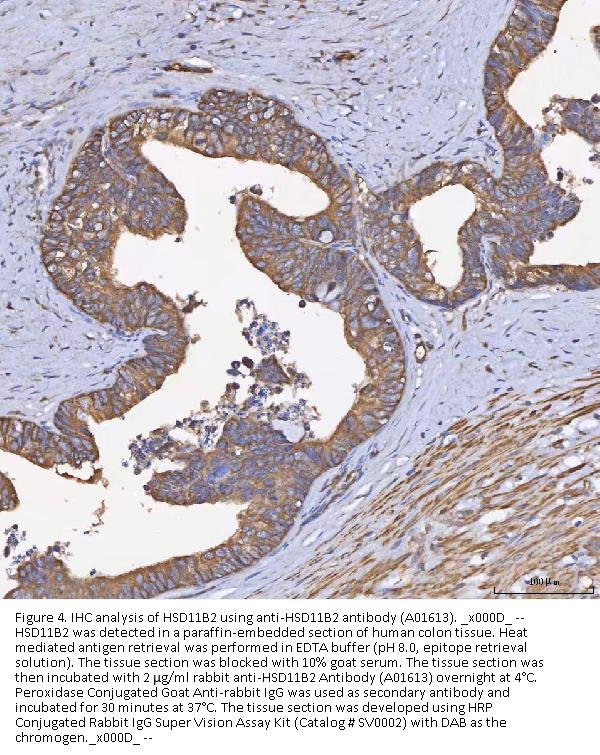

Immunohistochemistry(Paraffin-embedded Section), 2-5 μg/ml, Human

Boster Bio Anti-HSD11B2 Antibody Picoband® catalog # A01613. Tested in ELISA, Flow Cytometry, IF, IHC, WB applications. This antibody reacts with Human. The brand Picoband indicates this is a premium antibody that guarantees superior quality, high affinity, and strong signals with minimal background in Western blot applications. Only our best-performing antibodies are designated as Picoband, ensuring unmatched performance.